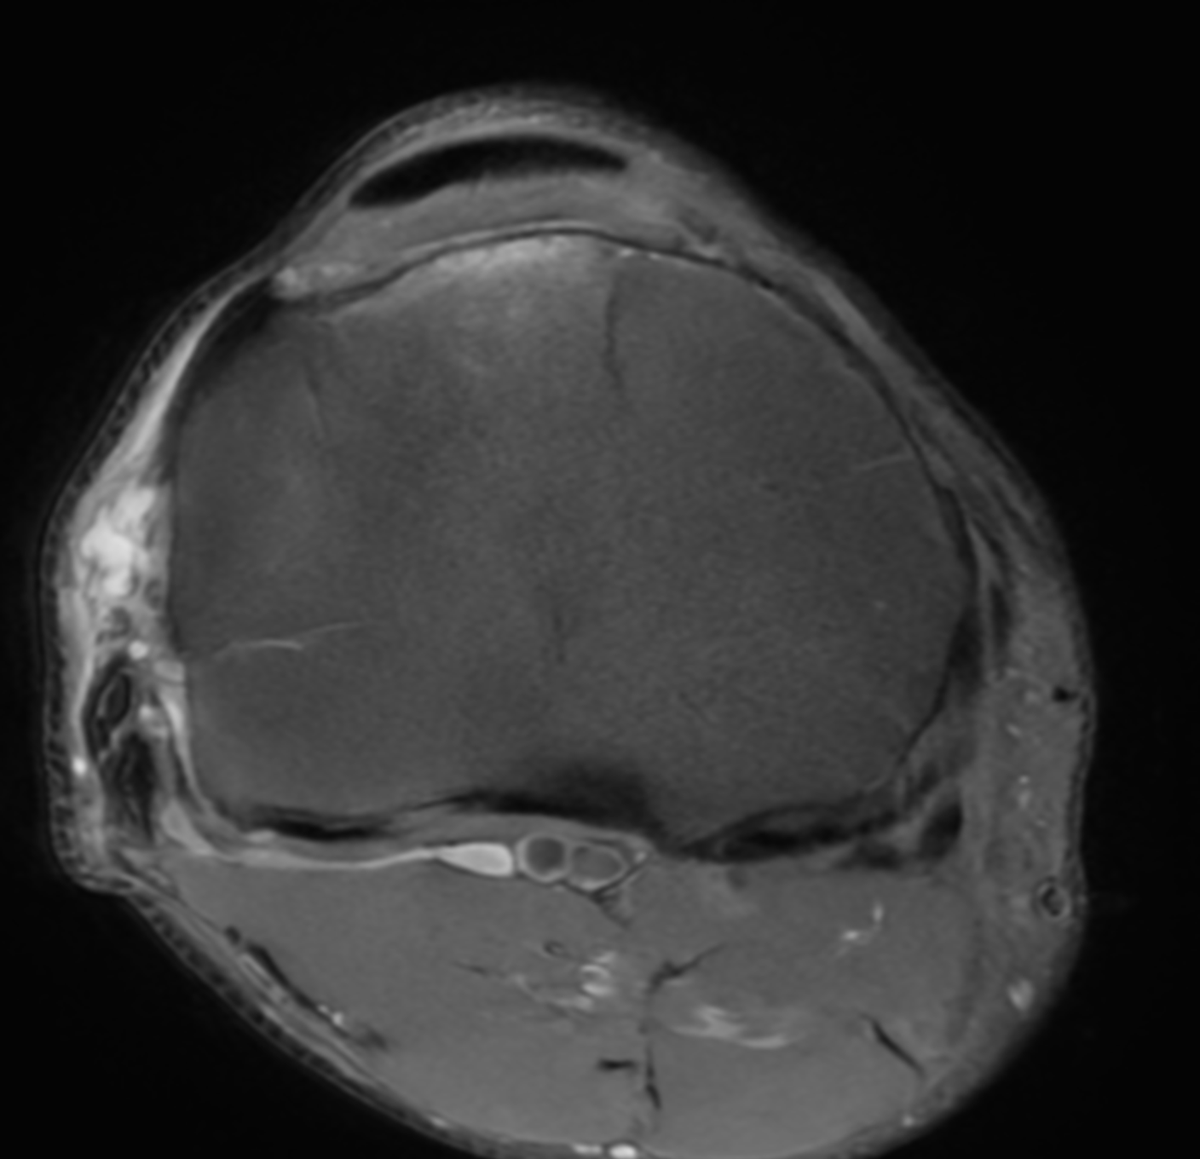

60 yo runner. Also lifts 3x/week. Stable lateral meniscus tear and a small cartilage defect for 10 years. New pain.. worse. Mostly anterior, anterolateral. Pain with loading, jumping, etc... but on landing, not the jump. in other words... axial load hurts.

New MRI: mostly anterior BME deep to PT insertion.

Stress reaction from the tendon or load??